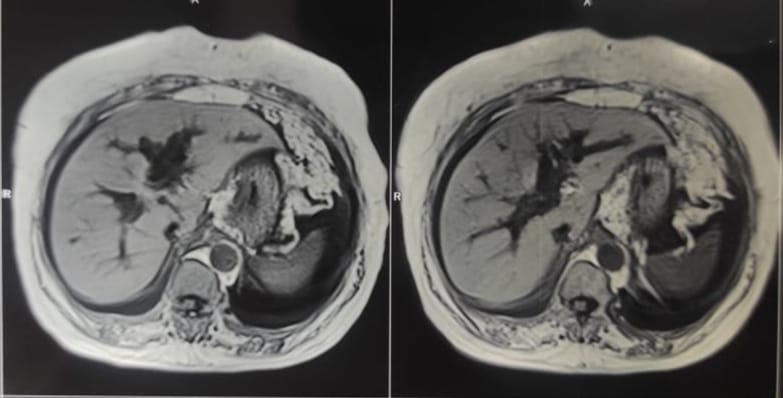

MRCP :

CT abdomen:

Obstructive jaundice secondary to CBD stricture/cholangio carcinoma